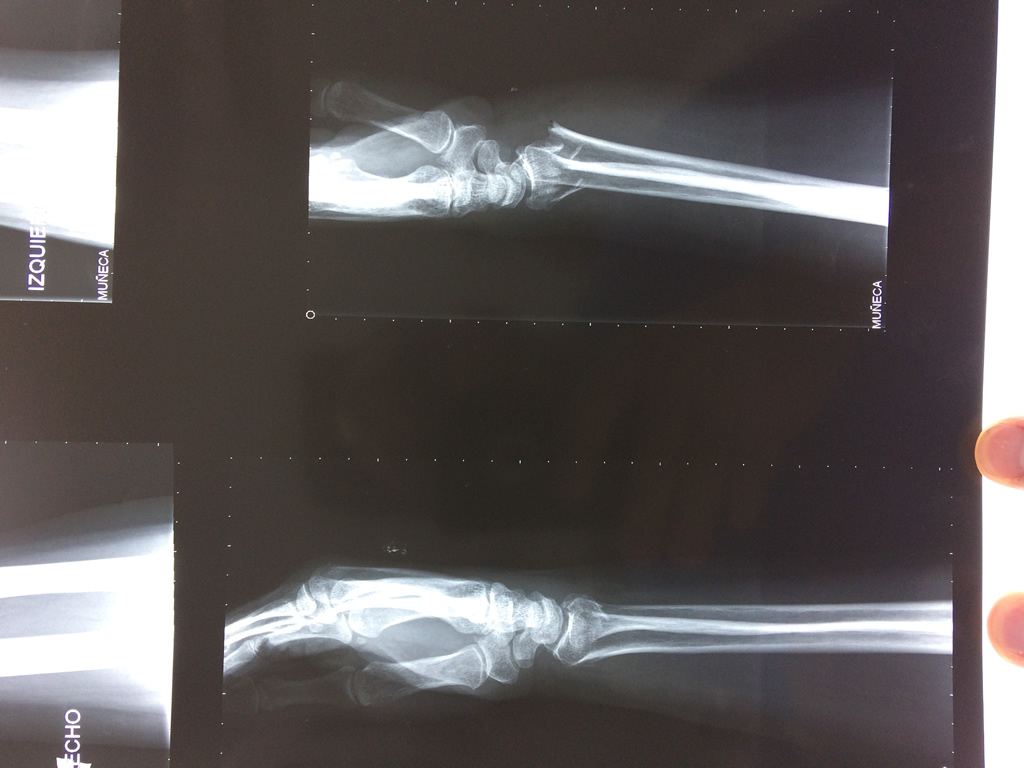

Cirugía de Fémur - Cirugías de Muñecas y Manos

Los procedimientos más comunes en cirugía de la mano son aquellos destinados a reparar traumatismos, incluyendo lesiones de tendones, nervios, vasos sanguíneos, y articulaciones; huesos fracturados; y quemaduras, cortes, y otros daños de la piel.